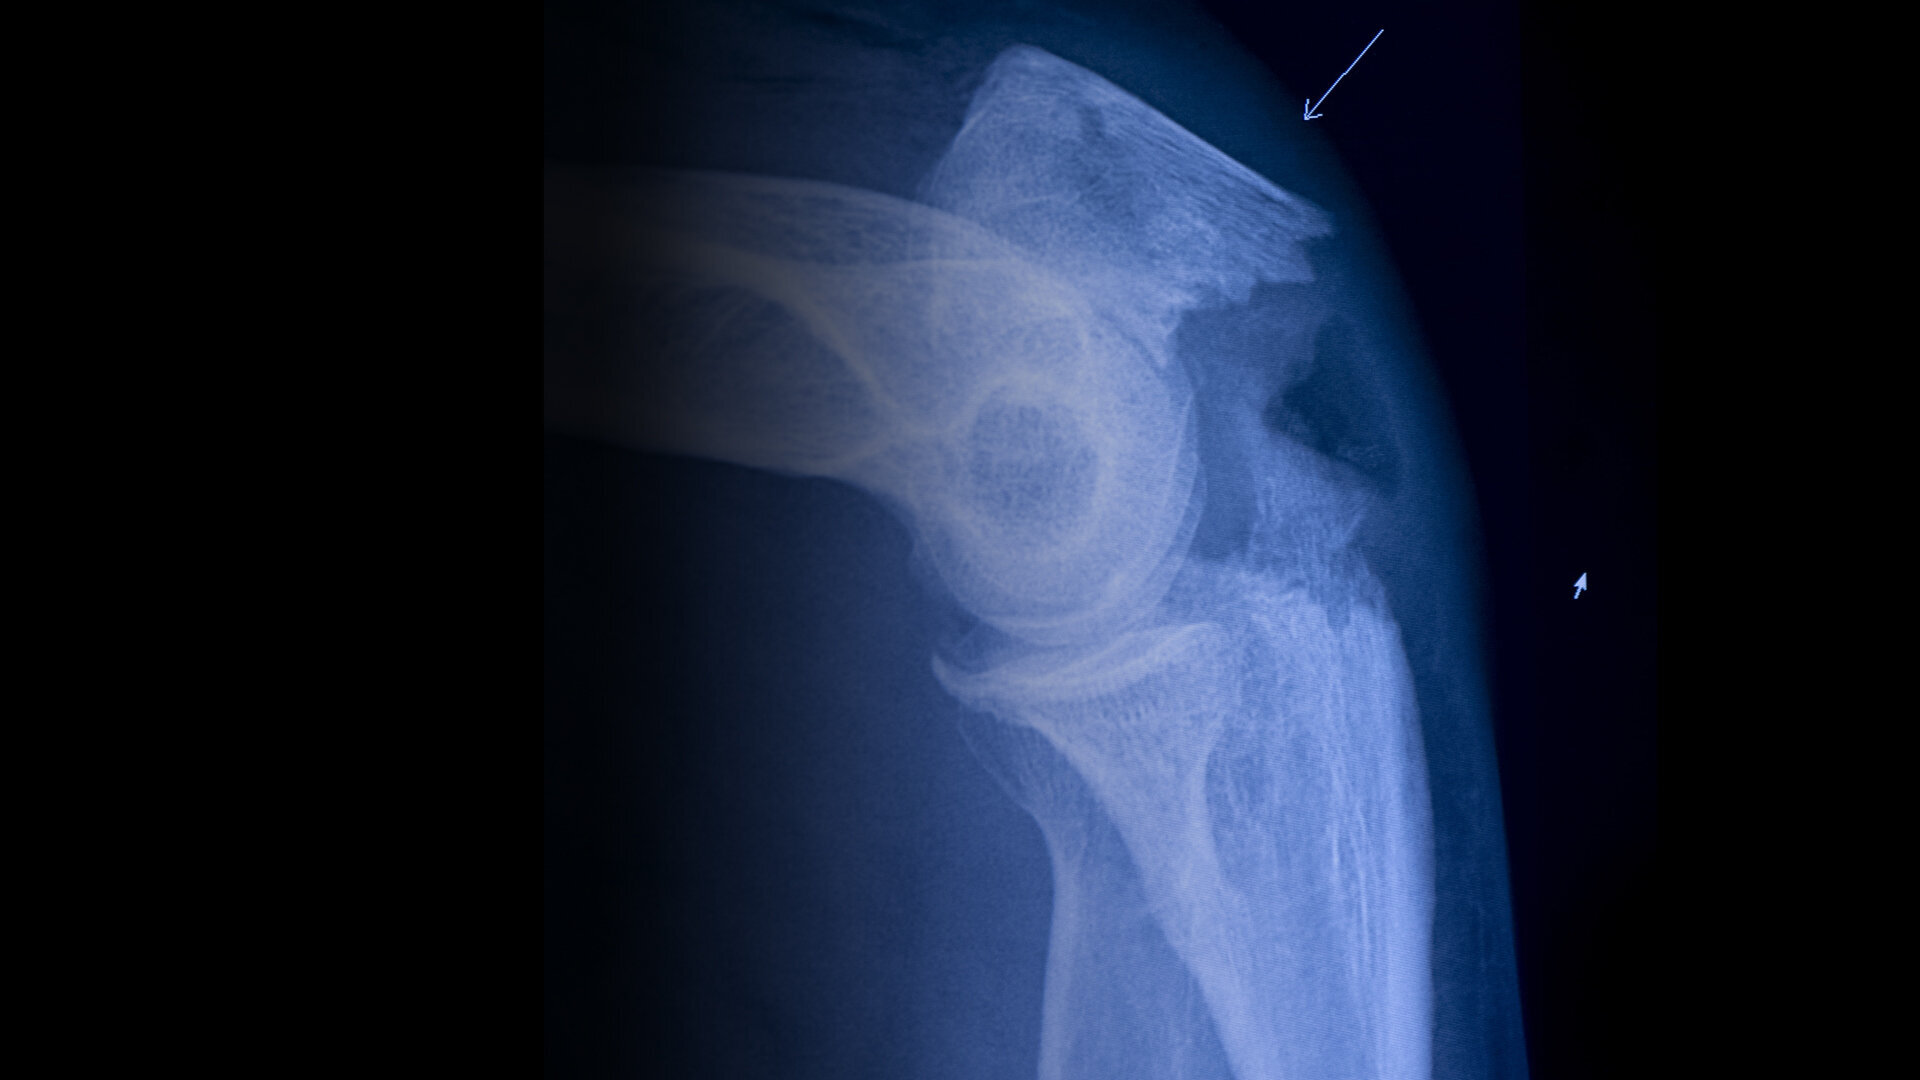

#Fall Når eldre mennesker faller, starter problemene.Leder, Barth TholensEn høy pris for et lite uhellLeder SykepleienHvorfor snakke om fall?Regjeringen mislyktes i å redusere antall hoftebruddNyheter– Jeg er redd for å bli rullestolavhengigNyheterPasientene får effektiv oppfølging på osteoporoseklinikkenFagutviklingHvorfor faller eldre?FagutviklingVil redusere hoftebrudd med minst 500 i året med egne bruddsykepleiereNyheter– Jeg har fått en psykisk knekkNyheterFallpoliklinikk: Sykepleier Elisabet Sigurjonsdottir jakter snubletråder hver dagNyheterReduserte hoftebrudd med 40 prosent på fire årNyheter– Jeg har begynt å se meg over skuldra når jeg er i byenNyheterHva innebærer en fallskade?Fagutvikling– Tenk fallforebygging tidligNyheterJudoklubben lærer eldre å falle som en bananNyheterDa jeg ikke var derDebatt– Smerten var så grusom at jeg nesten ble bedøvdNyheter– Jeg savner å gå på ski. Sykle, løpeNyheterKan noen fall skyldes medisinene?Nyheter10 millioner kroner utbetalt etter fallskaderNyheterSensorene varsler når «Anna» står oppNyheterUtgave på papirKjøp Sykepleien på papir herNyheter